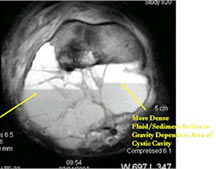

- The cystic spaces filled with hemorrhagic material leads to the presence of fluid-fluid levels on MRIs (so called ABC-like changes or telangiectatic change)

MRI/CT:

- Fluid-fluid levels secondary to cystic cavities filled with blood products. The sediment from blood products settle to the gravity dependent area of the cavity and the fluid component floats to top thus forming a fluid-fluid level.

- MRI and CT are also useful for demonstrating the local extent of the tumor and any soft tissue mass